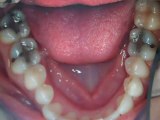

Crooked teeth -Veneers Austin,Tx-Lakeway Before an

Here's some before and afters of Porcelain Veneers used to straighten teeth. Visit www.lakewaysmiles.com for more information.